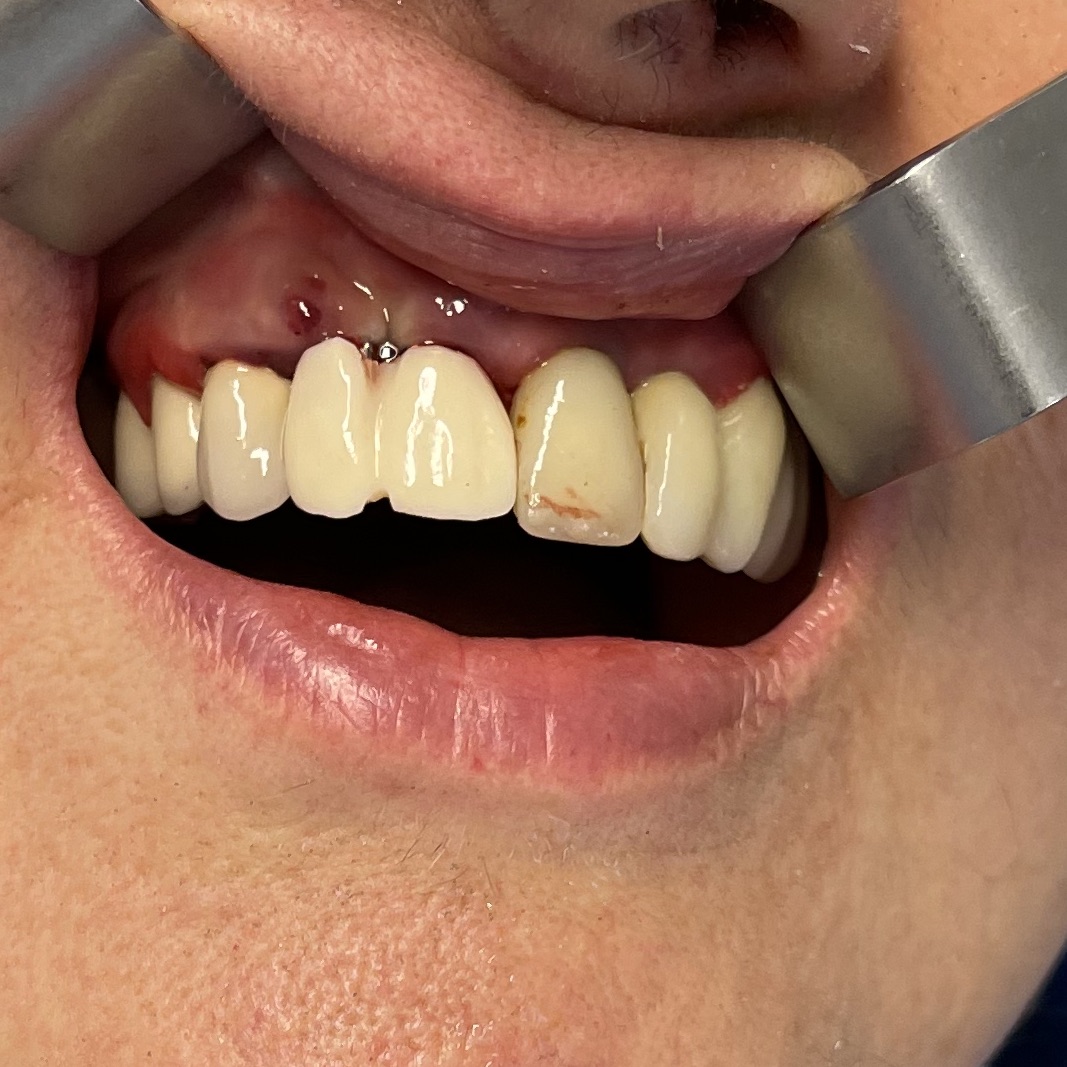

Zona dentale: 11 12

Situazione estrattiva: postestrattivi immediati

Carico occlusale : immediato leggero

Descrizione intervento

Complicanze: assenti